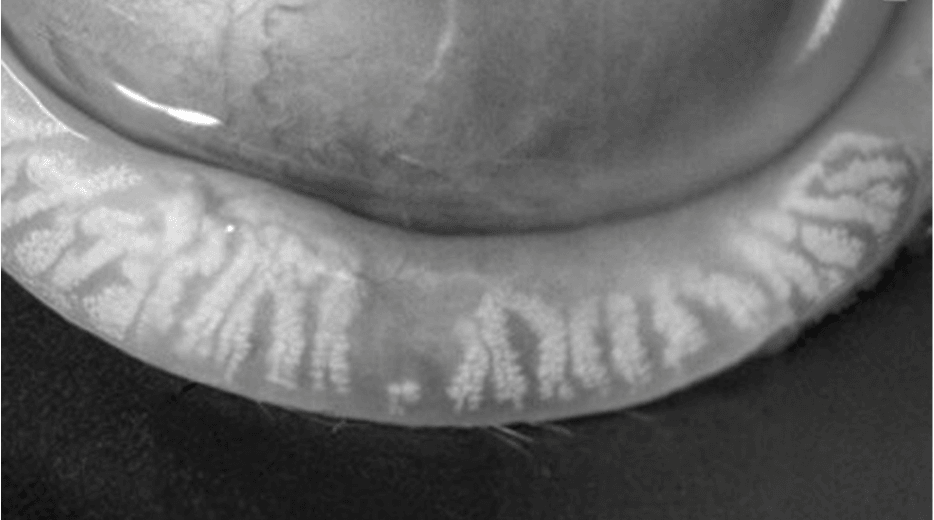

Meibomian Gland Dysfunction (MGD) Assessment

Meibomian Gland Dysfunction (MGD) can be

thoroughly assessed through precision diagnostics

MGD is a chronic, progressive,

and obstructive condition.

Maintaining the healthy function and structure of the meibomian glands

before dry eye symptoms appear is crucial.